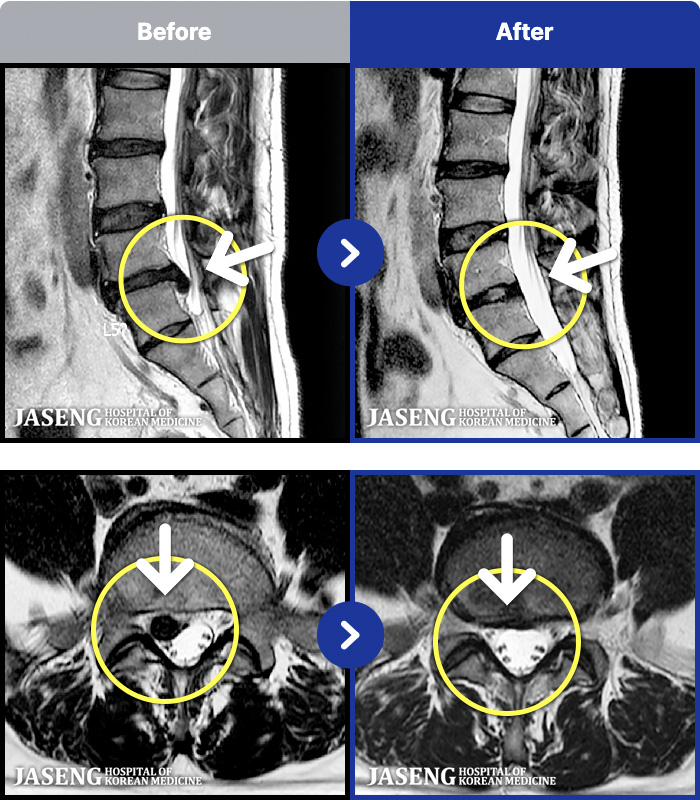

188 MRI ũ ʸ Ȯϼ.

ȯںп Ǹ ǿ ԿǾ, ο ġ ۿ Ƿ ġḦ Ͻñ ٶϴ.